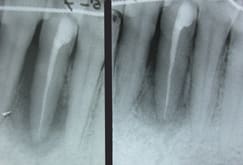

si ...alors la suite ....

cicatrisation à 6 mois

par contre je suis persuadé qu'il ne faut pas sonder pas irriguer plus qu'il ne faut surtout si comme dans le cas ou celui de Carole la composante occlusale prend le dessus sur la composante infectieuse .. Si abcès en urgence atb probabiliste de type metronidazole ...pas de tests . J'ai mis volontairement la sonde sur la photo pour montrer qu'à 6 mois seulement j'avais sondé pas avant.au niveau muqueux c'est cicatrisé mais au niveau osseux il faut encore 3 mois au moins

dans un cas comme le mien je fais traiter l'endo en premier puis approche paro . Mon problème majeur est que je ne sonde pas donc diag differentiel plus délicat entre endo pure et paro pure ou endo paro .vu le contexte la survie de la dent est en cause donc je préfère faire une endo pour rien plutôt qu'un echec ou qu'une recidive qui peut être mal tolérée .....

sur le plan pratique contention 1 - endo 2 - contexte paro 3